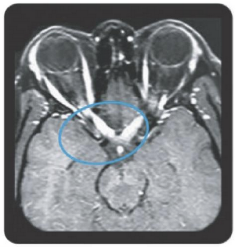

Area postrema syndrome is a core clinical characteristic of NMOSD that can appear both at disease onset and throughout the clinical course7

- The spectrum of NMOSD symptoms is broad and includes nausea, vomiting, and intractable hiccups7,8

- 4 out of 10 NMOSD attacks of the area postrema include all 3 symptoms7

- Due to symptom severity, ~80% of patients with NMOSD-related area postrema syndrome are hospitalized7